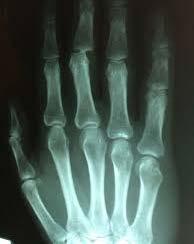

Medicinsk billeddannelse - stiller skarpt på din sygdom og behandling

Sundhedssektoren er forbruger af noget af den mest avancerede højteknologi til diagnostik, monitorering og behandling ikke mindst i forbindelse med patientspecifikke forløb. Samtidig er markedet for sundhedsteknologi globalt ekspanderende,” siger DTU´s prorektor Rasmus Larsen.